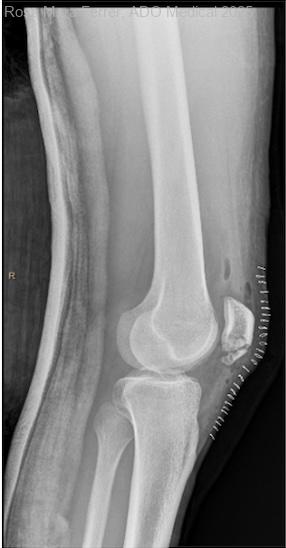

Dolor en paciente con rotura aguda del tendón rotuliano

Paciente de 23 años acude a urgencias por dolor en rodilla derecha. Había caído de aproximadamente 2 metros de altura en su domicilio y posteriormente presentaba dolor en rodilla derecha con importante edema, mínima erosión superficial de...